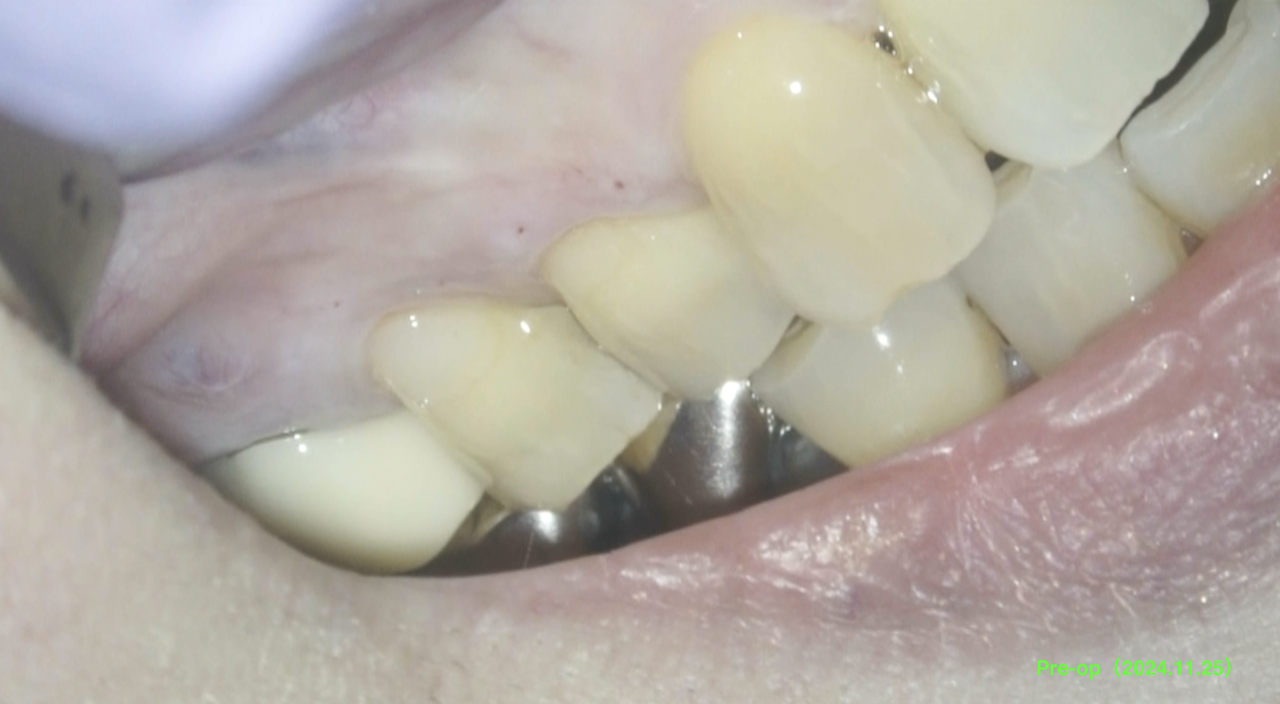

Pre-op Endo test(2024.11.25)

#3にSinus tractと圧痛がある。